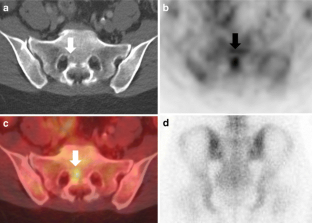

Fig. 2